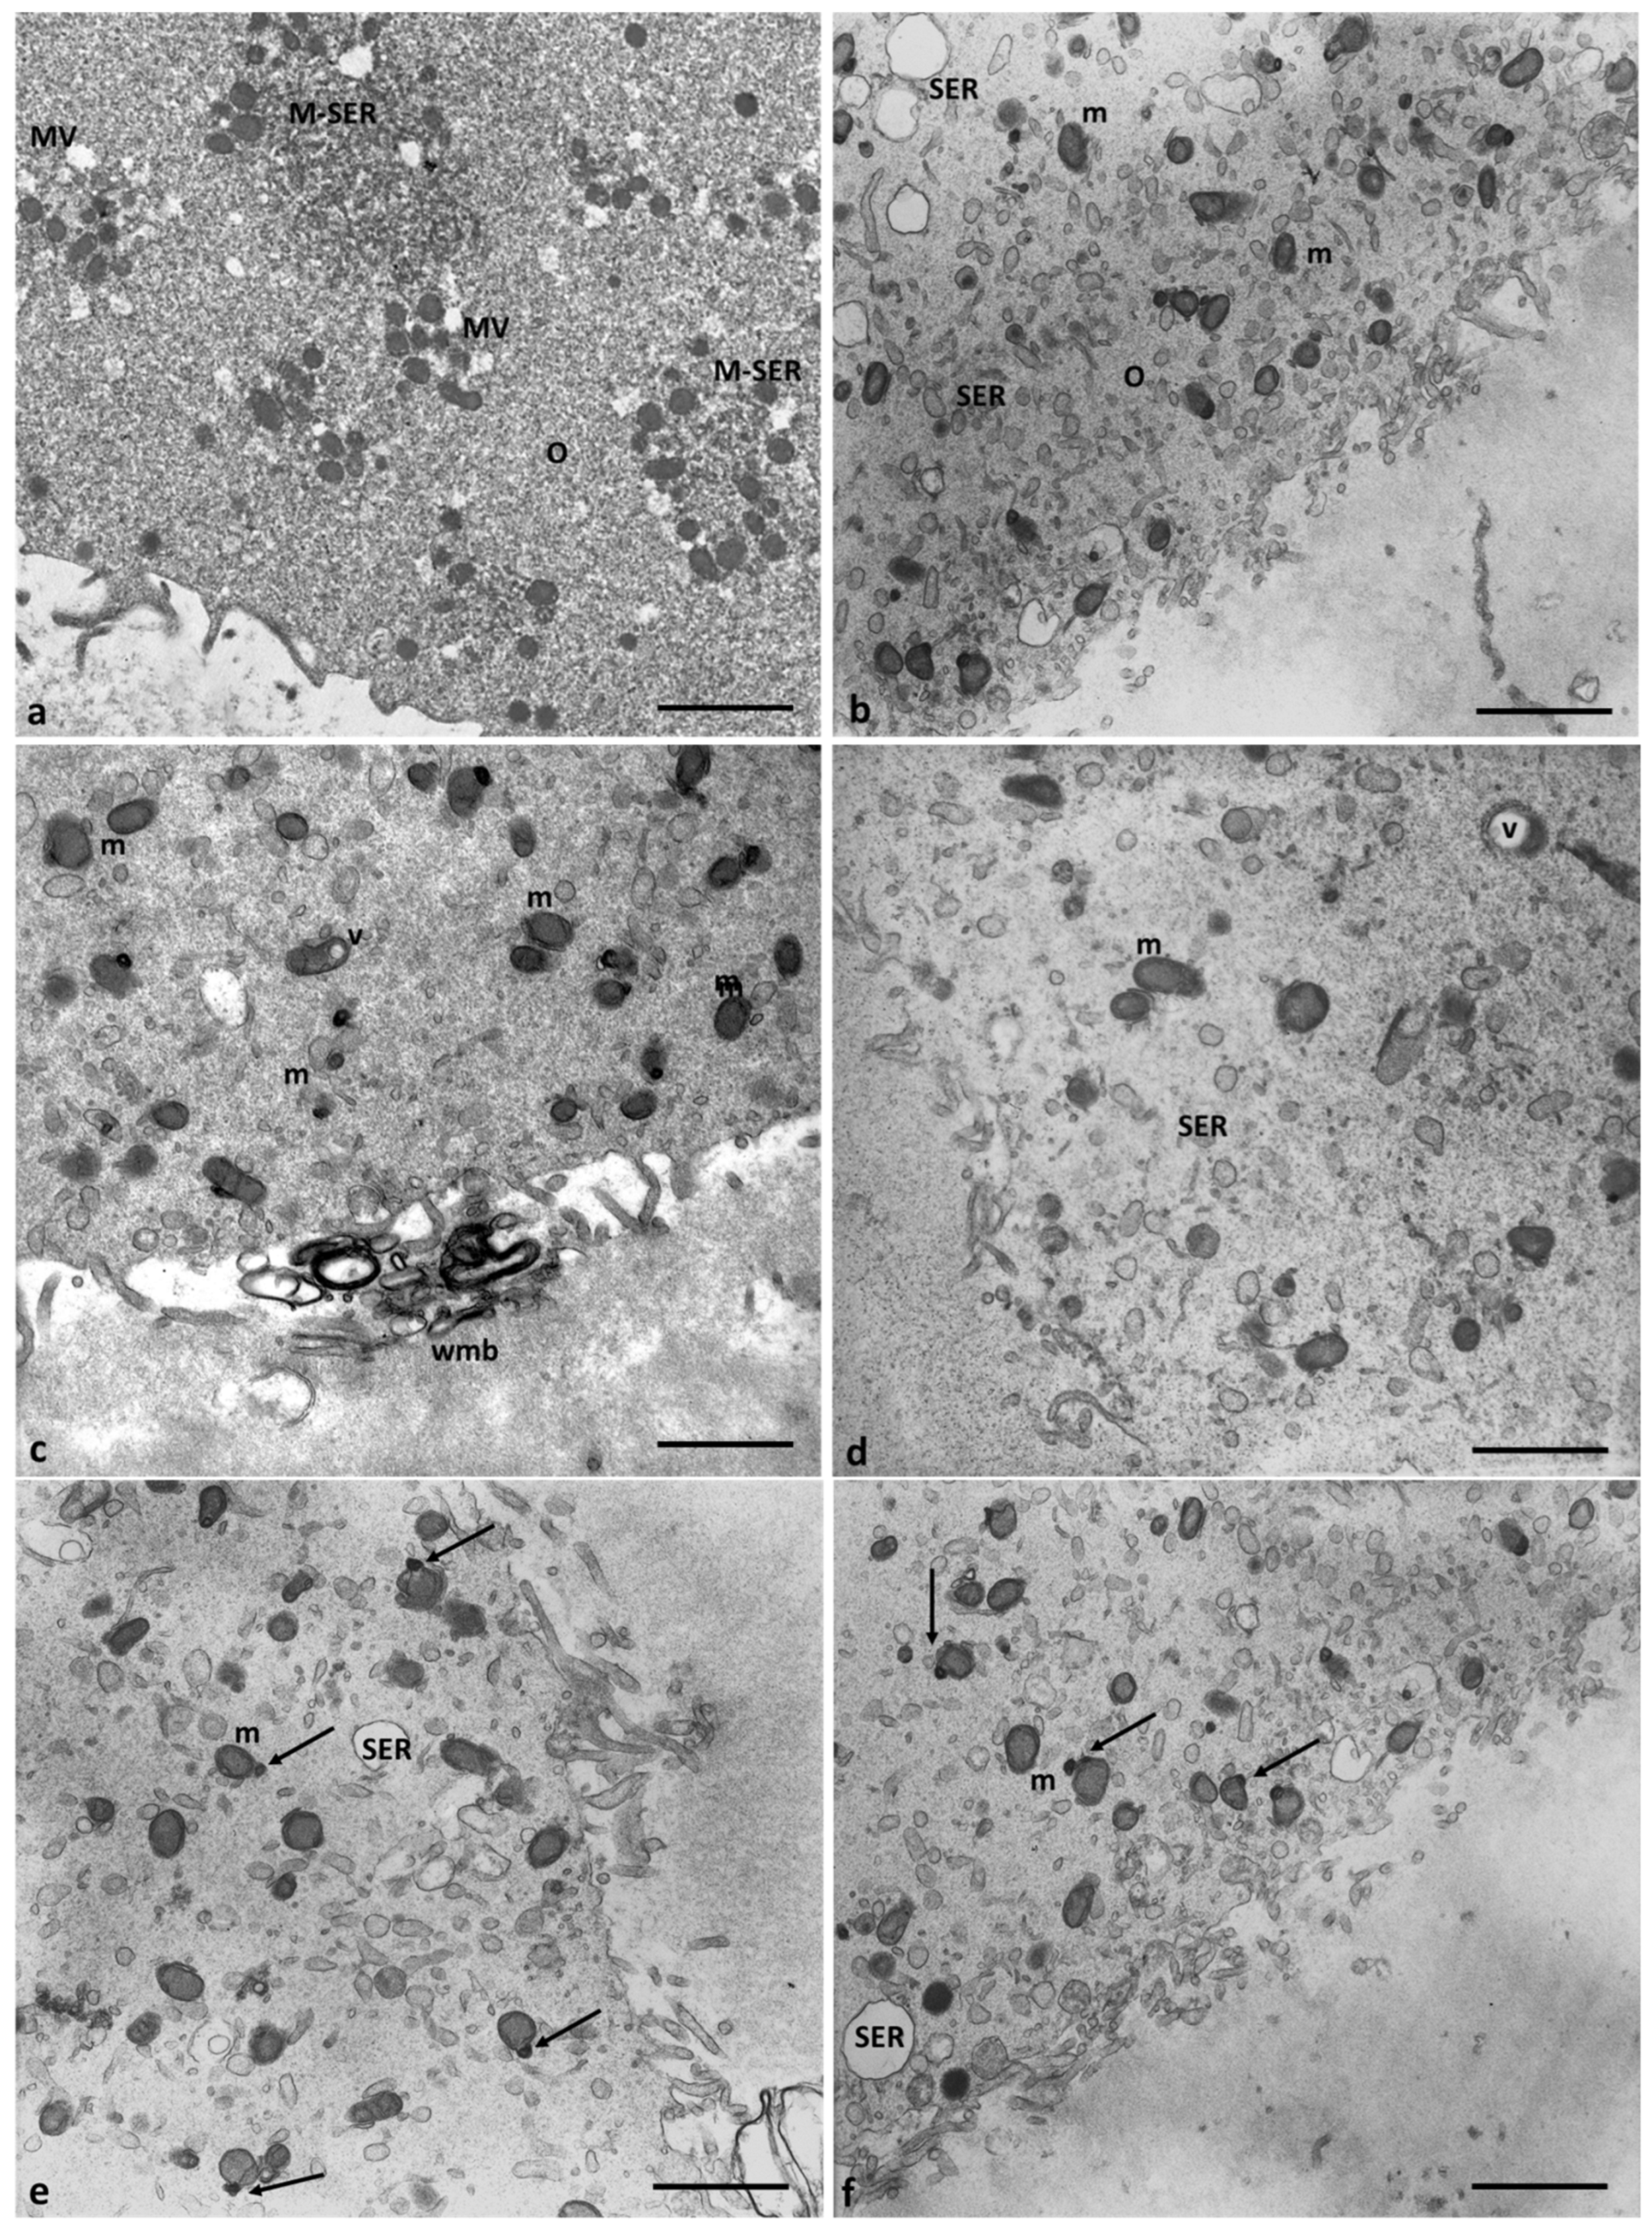

3.2. Electron microscopy

4.1. Oocyte- ultrastructural changes heavy metals-dependent

4.2. Cumulus cells ultrastructural changes heavy metals-dependent.